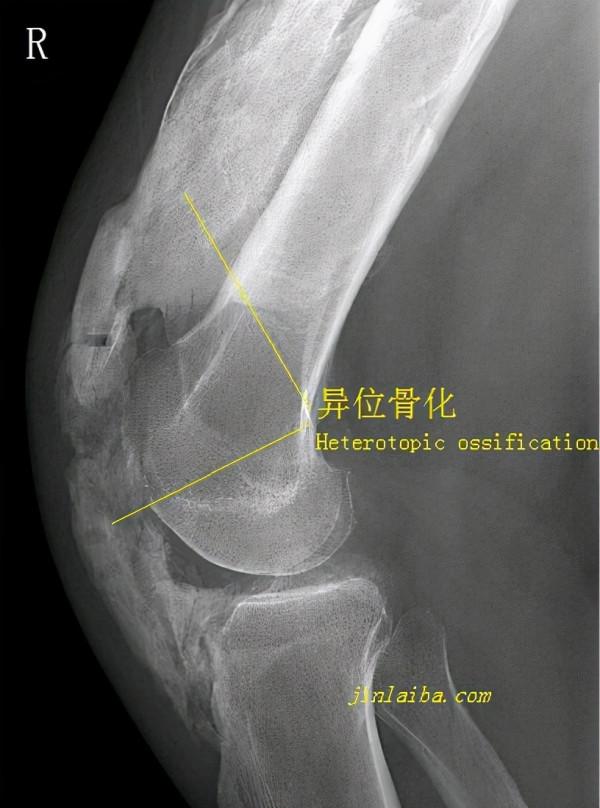

所謂異位骨化,說白了就是在不應該出現骨骼的位置生長了骨骼,常出現於創傷後的軟組織,也可見於癱瘓處的大關節。發生骨折或軟組織損傷後的髖、肘、膝、肩等大關節,其受損部位附近的軟組織極易在癒合過程中形成異位骨化。

異位骨化的形成機制尚不完全明朗,但可以猜測這是一種骨骼增殖功能的“意外表現”。骨骼和肌肉、韌帶、軟骨、面板等組織一樣,都屬於結締組織,其生長的底層機制相同,不同之處在於密度、成分及組織形式。骨骼的生成主要依賴於成骨細胞、鈣鹽及血供,當軟組織及骨折發生後,這三個條件得到了極大化的滿足,如果再加上治療不當、活動不足等因素,很快就會在錯誤的位置生長出異常的骨骼。